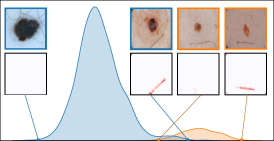

In this section, we leverage latent bias representations, either via directions or individual neurons, to retrieve biased samples and measure how well bias samples are separated from clean samples. We compute bias scores as defined in Eq. 1 by projecting latent activations onto the bias direction. As we are mostly interested in the ranking capabilities, i.e., artifact samples should be assigned higher bias scores than clean samples, we measure Area Under the Receiver Operating Curve (AUROC) and Average Precision (AP), considering both real and controlled artifacts. For real artifacts, we evaluate retrieval using existing artifact labels, while we have ground truth information for controlled experiments. We train CAVs using Support Vector Machines (SVMs) on different layers of VGG16 and ResNet50 models for all datasets, reporting AUROC and AP on unseen test samples. Note, that while Pahde et al. [58] claim that classifier-based CAV computation can yield imprecise concept directions, they argue that SVM-CAVs are superior for predicting concept presence, the main goal of this experiment. In Fig. 7, we show the results for different layers of VGG16 and ResNet50 using single neurons (dashed line) and CAVs (solid line) as bias representation. Best neurons are selected using the validation set. The results indicate that CAVs generally outperform single neuron representations for sample retrieval, and the layer choice is crucial depending on the bias type. For instance, while CAVs for layers closer to the model heads can detect pacemaker samples, they fail for earlier layers.

6.4 Spatial Bias Localization

To spatially localize biases in input space with CAVs, we compute local explanations for the element-wise product of latent activations and concept direction (see Eq. 2). We use the controlled artifacts, specifically timestamp (HyperKvasir) and micropscope (ISIC2019) with ground truth concept localization masks for evaluation. We compute (1) the percentage of relevance within the ground truth mask and (2) the Jaccard index, or Intersection over Union (IoU), of the binarized localization mask with the ground truth. In Fig. 9, we report both metrics using CAVs computed on different layers of VGG16 and ResNet50. The layer choice for concept representations is key, as for example middle layers perform better to localize timestamps and earlier layers are more effective to localize the microscope. In comparison with Fig.7, we find that the optimal layer for bias localization may differ from the one for sample retrieval. Interestingly, the IoU for the microscope artifact is consistently low, as models primarily focus on the border of the circle instead of the entire area, as indicated by qualitative results in Appendix A.6.3. Unlike artifact relevance, the IoU metric also measures how much of the expected areas the computed mask does not cover.